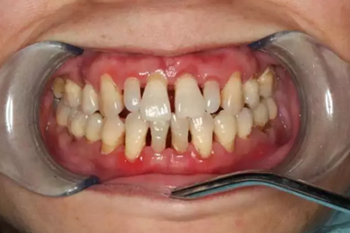

雖然起初沒有任何的不適癥狀,但是會使牙齦由健康慢慢變?yōu)檠装Y狀態(tài):充血紅腫、由堅韌的質地慢慢變得很脆,一旦受到刷牙和咀嚼時的機械摩擦就極易出血。

牙齦碰不得,一碰就出血。這是咋回事?